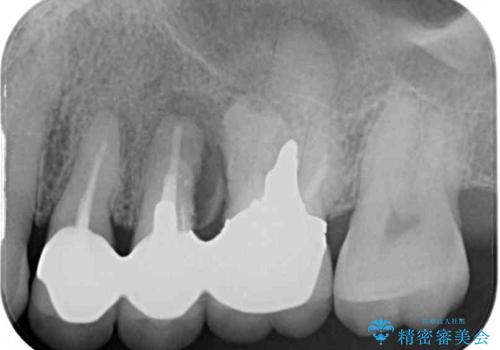

レントゲン写真より、歯が破折している可能性が示唆され、歯槽骨が大きく欠損している様子が分かりました。

3歯のクラウンを除去し、破折が疑われる歯をチェックしたところ、予想通り破折していたため、抜去することとしました。